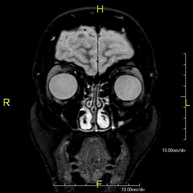

- RM Órbitas

Prueba diagnóstica no invasiva que consiste en la obtención de imágenes de alta definición anatómica de las órbitas mediante el empleo de un campo electromagnético y ondas de radio (con un emisor y un receptor). No utiliza radiación ionizante. Indicaciones: visión doble, traumatismo, sospecha de tumor, hipertiroidismo.